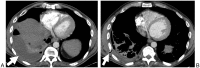

Infectious, traumatic, or neoplastic processes in the chest often result in fluid collections within the pleural, parenchymal, or mediastinal spaces. The same fundamental principles that guide drainages of the abdomen can be applied to the chest. This review discusses various pathologic conditions of the thorax that can result in the abnormal accumulation of fluid or air, and their management using image-guided methods.